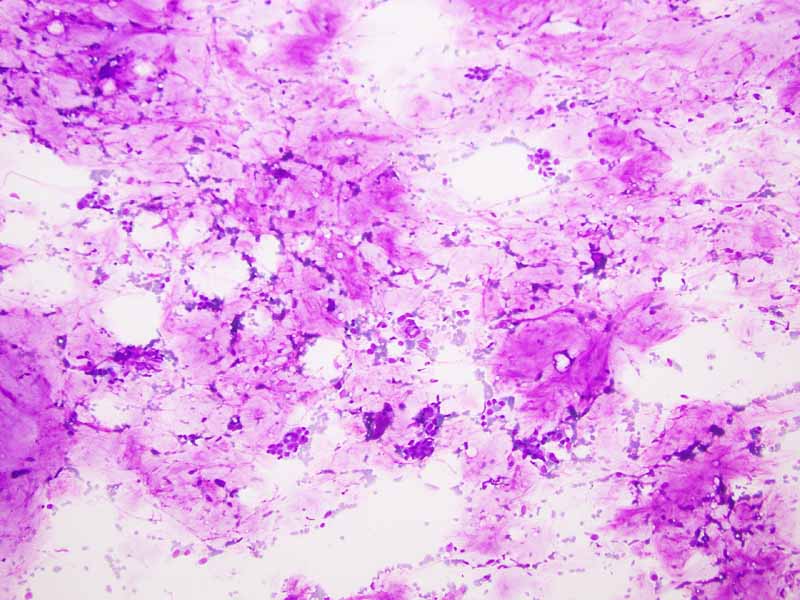

Cytology of the Case: The background is dominated by a substantial amount of mucoid material (Panel A) and admixed with these materials are small clusters of neoplastic cells. Some delicate blood vessels are also present (Panel B). A small number of tumor cells are adhered to these blood vessels but there is a lack of genuine papillary arrangement. The cells are epithelioid and contains a moderate amount of cytoplasm (Panel B, C, D, E, and F) that are finely vacuolated (Panel D and F) in some of them. The neoplastic cells are rather adhesive to each other. The nuclei are hyperchromatic and without pseudonuclear inclusion in most of them. There is no prominent nucleoli A minute amount of tissue is present in the cell block (Panel G). There is definitive gland formation. Some spindle neoplastic cells (S in Panel G) are also present next to the glandular structure. The nuclear features of these cells are identical to that of the glandular cells.

Clinical information: The patient was a 37 year-old woman with a deep 5.5 cm popliteal mass. An ultrasound guided FNA was performed and yielded the followings.